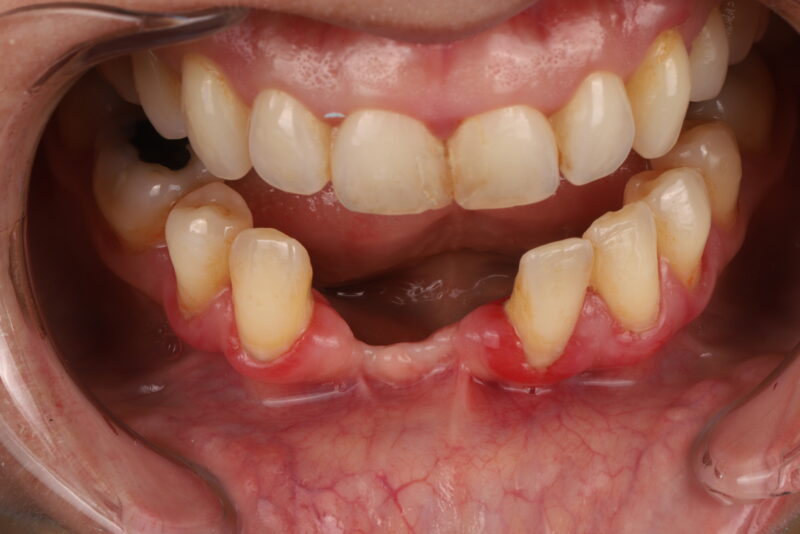

• intraoral pic

• I would remove them both and start over. The only way I’d restore 3 is if it was aware that it had less than 5 year prognosis. The issue was tissue thickness which was less than 2mm thick in all dimensions. I would just be honest with pt that their bone didn’t heal well and you’re concerned about long term prognosis. If they were hell bent I…

Read more